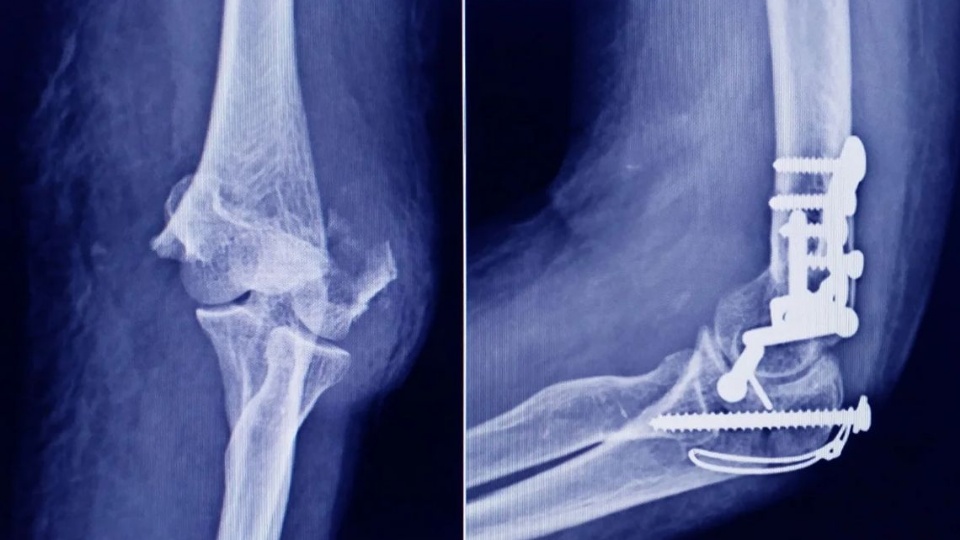

La Administración Nacional de Medicamentos, Alimentos y Tecnología Médica (ANMAT) emitió una alerta dirigida a la población por la detección de un tornillo apócrifo utilizado en cirugías traumatológicas, cuyo uso podría implicar un serio riesgo para la salud de los pacientes en los que sea implantado.

Según se informó, el tornillo corresponde a un producto que debería ser fabricado por Stryker Corporation, empresa registrada ante la ANMAT bajo el PM 594-139. Tras la inspección, la muestra recolectada fue exhibida a la responsable técnica de la compañía, quien confirmó que se trataba de una falsificación.

STRYKER 10 mm x 28 mm - Bioabsorbable - ACL Interference Screw - REF 234-010-067 - Lote 90905.